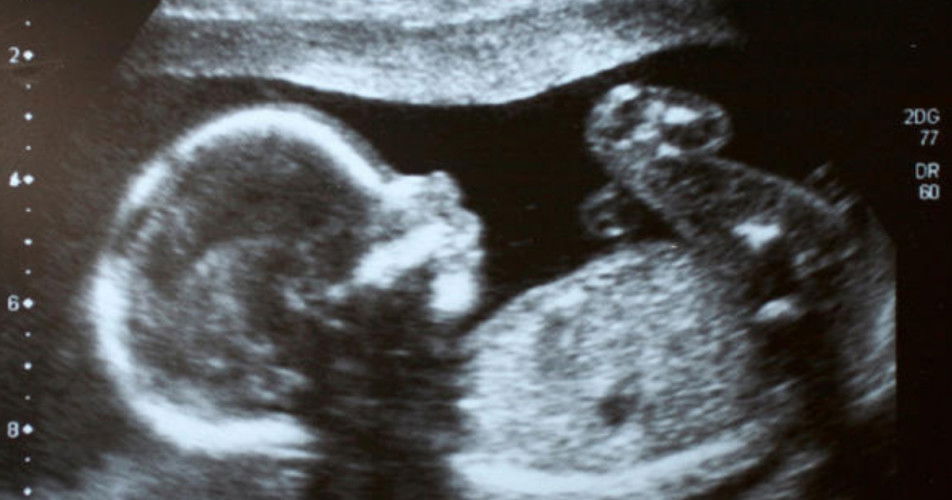

Scan jenis apakah menjadi pilihan anda ketika hamil? Tanda semua yang berkenaan.

2D

3D

4D

5D